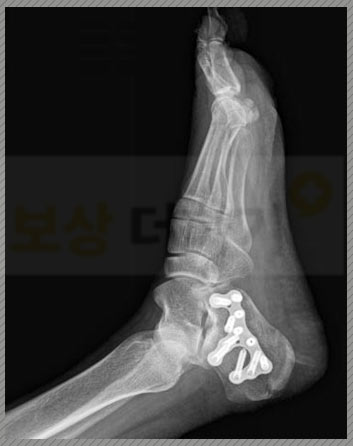

좌측 종골의 골절, 폐쇄성 S9200 종골 골절 진단을 받았습니다. 의뢰인의 경우, 자연적인 유합이 어렵다는 판단으로 관혈적 정복술 및 금속판을 이용한 내고정술을 시행 받게 되었습니다.

종골의 위치상 신체의 무게를 전달받을 수 밖에 없죠. 따라서 이렇게 치료를 잘 받더라도 일상생활에 상당한 제약이 생깁니다. 보행상의 장해, 발목 관절의 운동장해 등 여러 후유증이 남게 되는데요 의뢰인 역시 원상태로의 완전한 회복이 어려웠습니다.